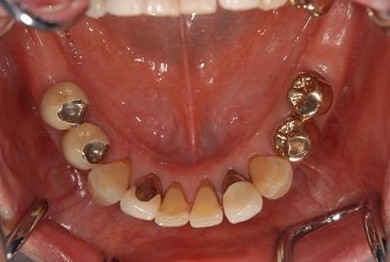

インプラントの症例写真 IMPLANT

| 治療内容 | インプラント8本(抜歯即日スピードインプラント、サイナスリフト)、ハイブリッドセラミック8本 | ||||||||||||||||||||||||||||||||